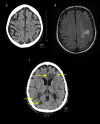

BACKGROUND Percutaneous catheter radiofrequency ablation (RFA) and cryoablation of the left atrium and pulmonary vein ostia have become successful therapeutic modalities in the management of atrial fibrillation. Atrio-esophageal fistula is a rare complication. Awareness of complication risk is imperative because without prompt diagnosis and urgent surgical intervention, the outcome is often fatal. We present 3 cases of atrio-esophageal fistula following percutaneous catheter radiofrequency ablation (RFA). CASE REPORT Case 1: A 72-year old white male presented 27 days after percutaneous RFA for atrial fibrillation with fever, altered mental status, and melena. Esophagogastroduodenoscopy (EGD) revealed a 1-cm defect in the mid-esophagus. Upon thoracotomy, severe hemorrhage ensued from a concomitant injury to the left atrium. Multiple attempts to repair the left atrial perforation were unsuccessful and the patient died. Case 2: A 71-year old white male presented 29 days after percutaneous RFA for atrial fibrillation with fever and tonic-clonic seizure. Recognition of possible atrio-esophageal fistula was considered and confirmed on thoracotomy. Surgical fixation of the left atria and esophagus were performed. The patient survived and was discharged to a skilled care facility. Case 3: A 75-year old white male presented 24 days after percutaneous RFA for atrial fibrillation with chest pain. An echocardiogram revealed a large pericardial effusion and pericardiocentesis was performed. Despite aggressive measures, the patient died. The autopsy demonstrated a communicating esophageal fistula with the right pulmonary vein. CONCLUSIONS Clinicians tending to patients who have recently undergone atrial ablation need to be aware of atrio-esophageal fistula as a rare but highly fatal complication.